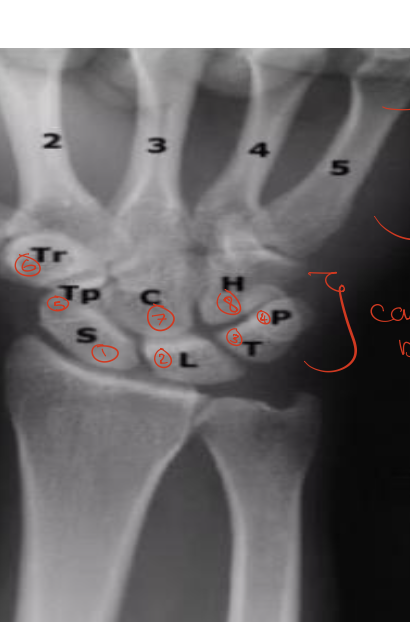

Identify the structures ? view? what joint ?

Wrist joint -AP

Scaphoid

Lunate

Triquetrum

Pisiform

Trapezium

Trapezoid

Capitate

Hamate